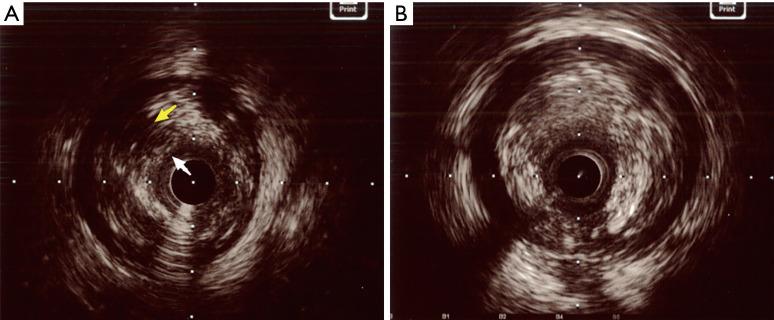

The data used in this prospective cohort research came from a prior multicenter prospective cohort study (ChiCTR1800019923). One hundred and thirteen consecutive STEMI patients were involved in our cohort study. Patients with STEMI who received primary percutaneous coronary intervention (pPCI) within 24 hours of symptom onset were included in the study and divided into two groups according to plaque characteristics derived from intravascular ultrasound (IVUS): a PR group and a non-PR group. The primary outcome was the incidence of no reflow or slow flow, the secondary outcome was major adverse cardiac events (MACEs) at 1-year follow-up.

This study enrolled 113 consecutive patients with STEMI [mean age 56 (range, 49-65.5) years; males 90.27%]. Of the 113 patients, PR was found in 93 (82.3%), while non-PR was found in 20 (17.7%). The PR group had a higher rates of plaque eccentricity index (64.28%±22.69% . 60.08%±15.54%; P=0.045), higher rates of lipid pool-like images (62.37% . 30.00%; P=0.008), and higher rates of tissue prolapse (22.95% . 13.33%; P=0.01). Compared with that in the non-PR group, the incidence of no reflow or slow flow was higher in the PR group after pPCI (26.88% . 5.00%; P=0.04). Multivariable logistic regression showed that PR [odds ratio (OR) =8.188; 95% confidence interval (CI): 1.020-65.734; P=0.048] was an independent predictor of no reflow or slow flow. Survival analysis revealed no significant differences in MACE incidence between the two groups at 1-year follow-up (7.61% . 10.00%; P=0.66). Furthermore, 29 patients with PR were treated without stenting, most of them were free of MACEs (27/29). MACE between subgroups of stenting and non-stenting had no significant differences (7.94% . 6.90%; P=0.86) in the PR group.